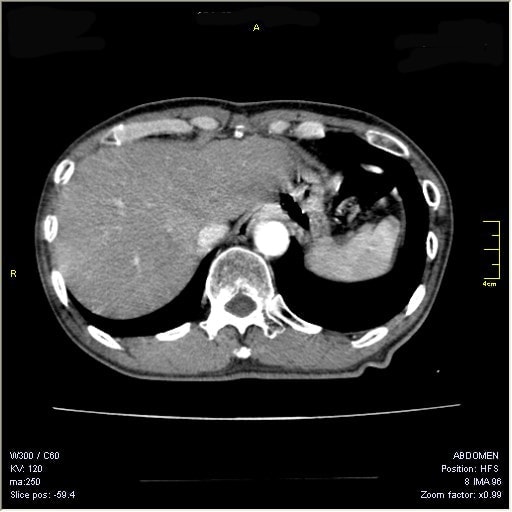

5. メタボ健診:オプションでCTを用いて内臓脂肪を正確に評価する方法があります。